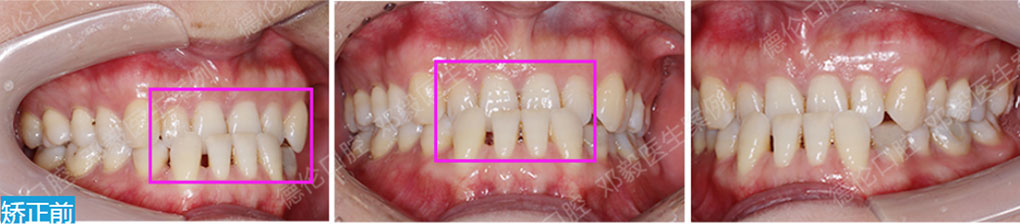

矯治前后對比

蛻變周期:上頜16個月,矯治效率提升30%,下頜12個月,矯治效率提升20%